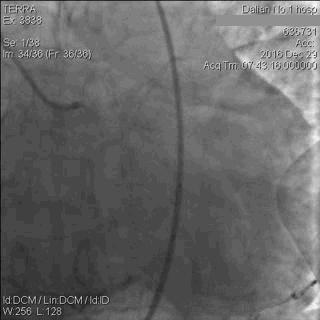

CAG显示,患者LAD中段以下闭塞;LCx近段轻中度狭窄,远段重度狭窄,钝缘支(OM)开口闭塞;RCA细小,且伴弥漫性轻中度狭窄,如图5。

图5 急诊CAG图像